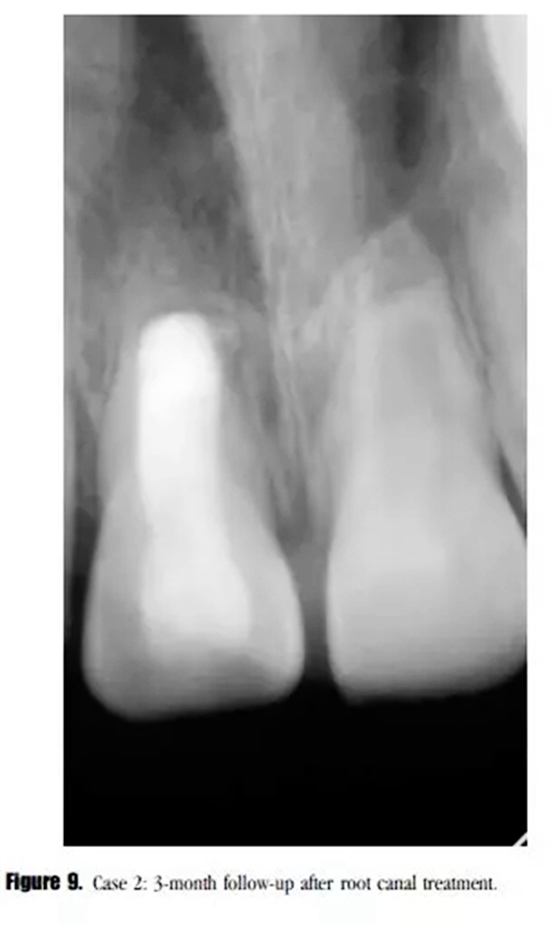

在3個月的隨訪中,患者癥狀消失,X線顯示透射區(qū)愈合(圖9)